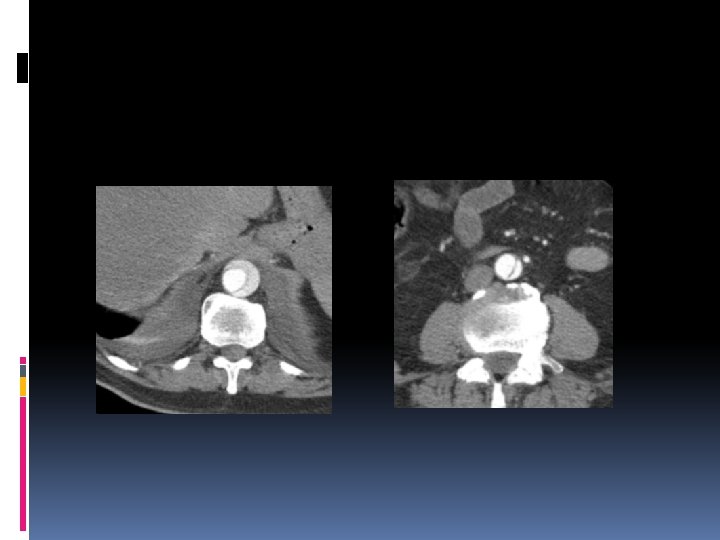

Protocolo de CT Tóraco-abdominal. Basal primero. 120 -150 cc, 3 -5 cc/s. Cortes de 5 mm. Estudio el fase arterial: �Sure star �Delay fijo (25 segundos) Valorar estudios en fase venosa (infarto e isquemia de diferentes órganos) Reconstrucciones VR y MIP

Hallazgos CT principales Flap Intimo-medial. Diferenciación del luz falsa y luz verdadera. Puerta de entrada ( 1 -5 cm superior a válvula aórtica en 65% ). Clasificación del tipo de disección. Oclusión de ramas de la aorta. Isquemia o infarto de órganos.

Diferenciación de luz falsa de verdadera. Luz falsa de >calibre. Calcificaciones de íntima en la luz verdadera. Bordes de ángulo agudo en luz falsa (signo del pico). Presencia de trombos en luz falsa. Flap secundario.